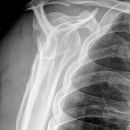

Schulter nach Morrison oder Outlet View

Indikation

v.a. Impingementsyndrom: Beurteilung des Akromions, des AC-Gelenks, evtl. hilfreich zur Diagnostik von Luxationen

Beurteilungskriterien

- Impingementsyndrom (2): Neigungswinkel des Akromions -> Je gebogener bzw. hakenförmiger desto höher ist die Wahrscheinlichkeit. Radiologische Befunde: Zystenbildung im Bereich des Tuberculum majus? Subchondrale Sklerosierung am Tuberculum majus oder subacromiale Osteophytenbildung? Verkalkungen im Verlauf der Supraspinatussehne?

- subacrominalen Raumes: normalerweise 1 - 1,5 cm, < 10 mm -> wahrscheinlich, < 6 mm -> sicher pathologisch